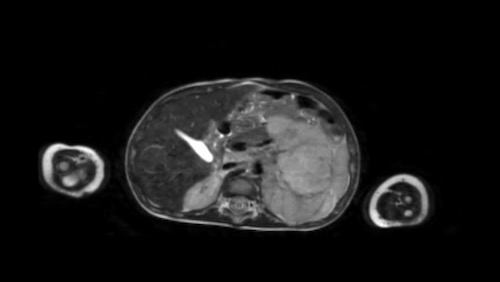

Mức độ lan rộng của khối u được đánh giá rõ ràng trên chuỗi xung TSE T2 weighted 3D theo mặt phẳng axial.

The left kidney is compressed and displaced caudally.

Có di căn hạch bạch huyết cạnh động mạch chủ (mũi tên vàng nhỏ).

Nguyên ủy của thân tạng và động mạch mạc treo tràng trên bị khối u bao quanh (đầu mũi tên).

Tĩnh mạch chủ dưới bị đẩy ra phía trước (mũi tên xanh).

Xẹp phổi hai bên ở vùng lưng thường được thấy trên MRI, vì việc kiểm tra được thực hiện dưới gây mê.